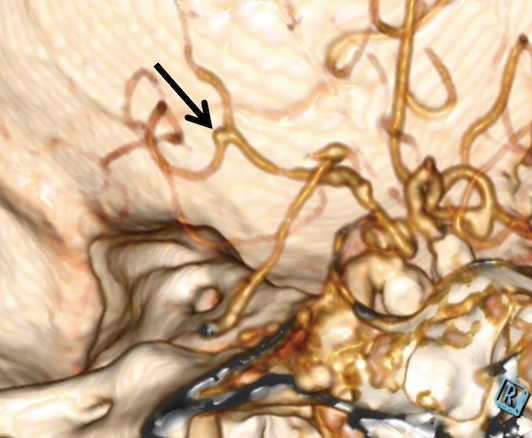

La détection et la caractérisation des anévrismes cérébraux sont essentielles, car le risque de rupture dépend de la taille, de la forme et de l'emplacement de ceux-ci. L'angioscanner est généralement le premier choix pour évaluer les anévrismes cérébraux. L'examen est très précis, mais les anévrismes cérébraux peuvent passer inaperçus de prime abord, en raison de leur petite taille et de la complexité du réseau vasculaire cérébral.

Le deep learning offre un énorme potentiel en tant qu'outil complémentaire pour une interprétation plus précise des anévrismes cérébraux. Dans cette étude, le Dr Long et ses collègues ont développé un algorithme entièrement automatisé et hautement sensible pour la détection des anévrismes cérébraux sur les images d'angioscanner. Ils ont utilisé des angiogrammes de plus de 500 patients pour former le système de deep learning, puis ils l'ont testé sur 534 autres angioscanners incluant 649 anévrismes.

L'algorithme a détecté 633 des 649 anévrismes cérébraux pour une sensibilité de 97,5%. Il a également trouvé huit nouveaux anévrismes qui ont été négligés lors de l'interprétation initiale. L’analyse statistique a révélé que l’aide au diagnostic était la plus prononcée chez les radiologues moins expérimentés. Les résultats suggèrent que l'algorithme utilisé est prometteur en tant qu'outil de soutien pour la détection des anévrismes cérébraux avec un potentiel pour être utilisé cliniquement comme deuxième avis lors de l'interprétation des images d'angioscanner cérébral. Pour le Dr Long, il présente un certain nombre d'avantages car l'ordinateur n'est pas influencé par des facteurs tels que le niveau d'expérience, le temps de travail et l'humeur qui affectent les performances humaines.

Des résultats à améliorer notamment dans les régions péri-osseuses

Il y trouve cependant certaines limites, comme l’omission de très petits anévrismes ou d’anévrismes situés à proximité de structures de densité osseuse ou quelques rares faux positifs. « En termes simples, le système de deep learning est destiné à aider les lecteurs humains, pas à les remplacer, conclut le Dr Long. À l'heure actuelle, le rôle de ce système d'apprentissage en profondeur, qui a été formé pour reconnaître les anévrismes, est de donner des suggestions au lecteur humain pour améliorer ses performances et réduire les erreurs. Le travail combiné du lecteur humain et du système informatique améliore la précision du diagnostic pour le bien du patient. »